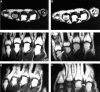

Objectives: To evaluate synovial membrane hypertrophy, tenosynovitis, and erosion development of the 2nd to 5th metacarpophalangeal (MCP) and proximal interphalangeal (PIP) joints by magnetic resonance imaging in a group of patients with rheumatoid arthritis (RA) or suspected RA followed up for one year. Additionally, to compare the results with radiography, bone scintigraphy, and clinical findings.

Patients and methods: Fifty five patients were examined at baseline, of whom 34 were followed up for one year. Twenty one patients already fulfilled the American College of Rheumatology (ACR) criteria for RA at baseline, five fulfilled the criteria only after one year's follow up, whereas eight maintained the original diagnosis of early unclassified polyarthritis. The following MRI variables were assessed at baseline and one year: synovial membrane hypertrophy score, number of erosions, and tenosynovitis score.

Results: MRI detected progression of erosions earlier and more often than did radiography of the same joints; at baseline the MRI to radiography ratio was 28:4. Erosions were exclusively found in patients with RA at baseline or fulfilling the ACR criteria at one year. At one year follow up, scores of MR synovial membrane hypertrophy, tenosynovitis, and scintigraphic tracer accumulation had not changed significantly from baseline; in contrast, swollen and tender joint counts had declined significantly (p<0.05).